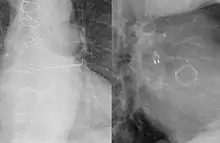

Radiograph showing an AtriClip attached to the left atrial appendage. Also visible is an aortic valve prosthesis.